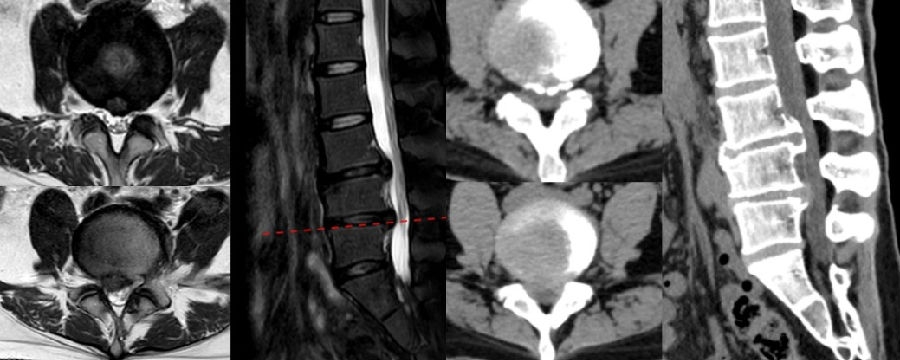

病例(减压不彻底,椎间盘残留)

男,73岁。

主诉:腰痛2年、加重伴右下肢疼痛麻木4个月,右足底、小腿后外侧为著。

术后右下肢症状无明显改善

八、医源性不稳定(0.88%)

发生率0.6%,明显低于开放式手术,小关节突关节损伤是主要原因。上腰椎(L1~L3)病变、存在狭窄椎板和脊柱矢状面失衡的患者减压过程几率更高。

病例(关节突损伤)

男,52岁。

主诉:腰痛20余年,双下肢疼痛10余年,加重4天。

查体:双侧直腿抬高试验及加强试验(-),双侧膝腱反射及跟腱反射未引出,Babinski征(-)。